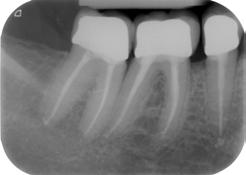

ábra: A kezelési terület izolálása érdekében kofferdám került felhelyezésre. A szuvas foganyag eltávolítását követően körkörös matricákat helyeztünk fel az endodonciai csonkfelépítés érdekében. – 10. ábra: A hiányzó falak kiépítése. – 11. ábra: A 45-ös és 46-os fog előkészítve és megtisztítva, készen állnak a gyökércsatorna-rendszer betömésére.

kutatunk [6]. A fenti faktorok mind hatással vannak a fog várható prognózisára. Az üreg teljes körű megtisztítása lehetővé teszi, hogy szükség esetén szabályszerűen el tudjuk végezni az endodonciai csonkfelépítést, amely a későbbiekben a kofferdámizolálás felhelyezhetőségét biztosítja. Amenynyiben lehetőségünk van rá, akkor minden esetben törekedjünk végleges endodonciai csonkfelépítés készítésére. Ez jelentős mértékben megkönnyíti az endodonciai kezelések kivitelezését és hozzájárul a gyökércsatornarendszer fertőtlenítésének szakszerű kivitelezéséhez. Az endodonciai csonkfelépítés elvégzésére fordított idő többszörösen megtérül a fog – gyökértömés elkészítését követően végzett – végleges felépítése során, mivel ekkor már gyakorlatilag egy minden oldalról ép falakkal körülvett üreg feltöltését kell csak elvégeznünk (8–12. ábrák).

ábra: A jobb alsó kvadráns helyreállítása után készült röntgenfelvétel.